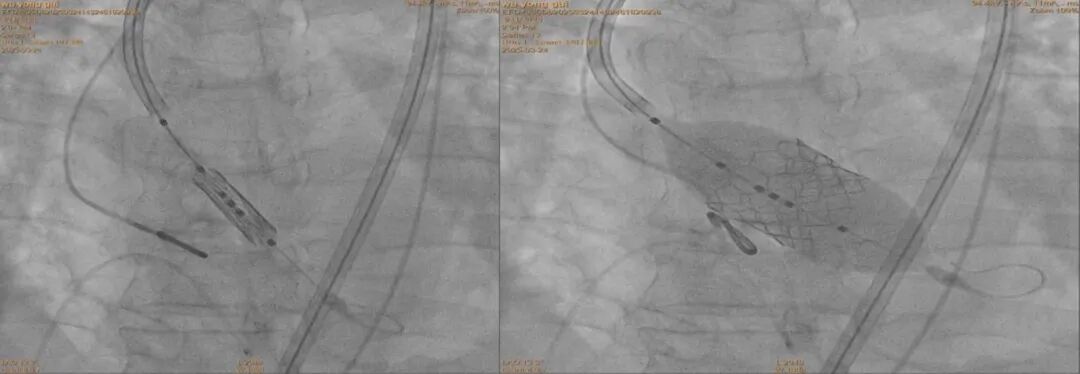

手术当天,心血管病科介入团队在石闯主任带领下为患者行主动脉瓣置换术(TAVR),通过CTA及超声精准测量瓣环结构,历时2小时成功完成瓣膜置换,术后患者血流动力学显著改善,未出现严重并发症。

主动脉瓣置换术(TAVR)通过股动脉穿刺,将压缩的人工生物瓣膜精准输送至病变的主动脉瓣位置并释放,替代原有狭窄瓣膜的功能。该技术无需体外循环和心脏停跳,手术创伤小、恢复快,尤其适用于传统开胸手术风险高的老年患者。

手术成功得益于心血管病科、麻醉科、影像科、超声科等多学科专家的紧密协作。术前通过三维影像重建精确评估瓣环解剖特征,术中采用经股动脉入路减少创伤,结合实时超声监测确保瓣膜定位精准。团队还制定了详细的风险应急预案,从术前评估到术后监护全程把控,最大限度保障患者安全。